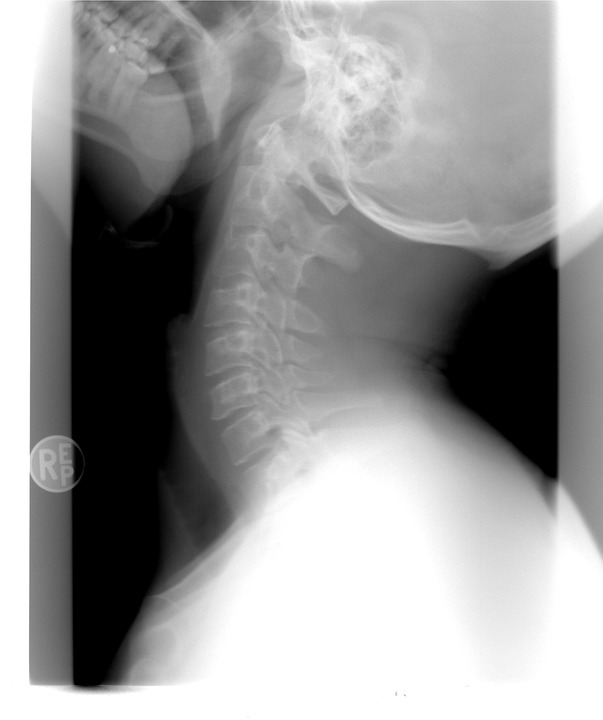

Your physician might also recommend a collection of imaging treatments to identify the cause of your pain in the back. These imaging treatments can consist of x-rays, bone scans, and CT scans. These imaging treatments can be useful, yet they aren't necessarily essential for a lot of situations of neck and back pain. If you have extreme pain in the back, your physician might suggest an injection. These shots can help to alleviate pain as well as reduce swelling.